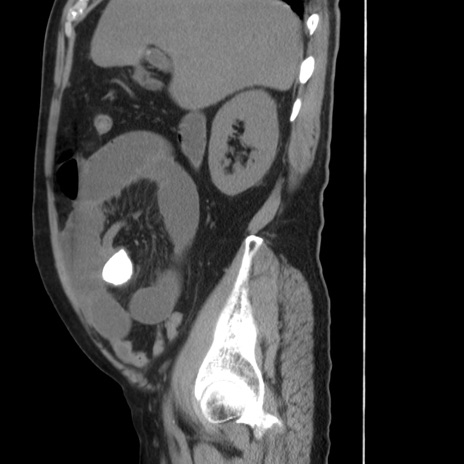

冠状断像

【症例】 60歳代男性

【主訴】 腹部膨満、嘔吐

【現病歴】5日前頃より倦怠感を認め食事量減少し4日前の朝嘔吐、食事摂取困難となった。 3日前近医受診し点滴施行され整腸剤などを処方された。 当日他院を受診し、腹部膨満著明、炎症反応の上昇(CRP10.8、WBC11200)あり、紹介受診となる。

【身体所見】 意識JCS1 受け答えがはっきりしないBP 111/57mHg、 P 67bpm、、BT35.2°C、SpO2 97%(RA)、 腹部:膨隆、打診で鼓音あり、全体的に圧痛有り、腸蠕動音(-)、反跳痛ははっきりせず。

【データ】WBC 11400、CRP 14.20